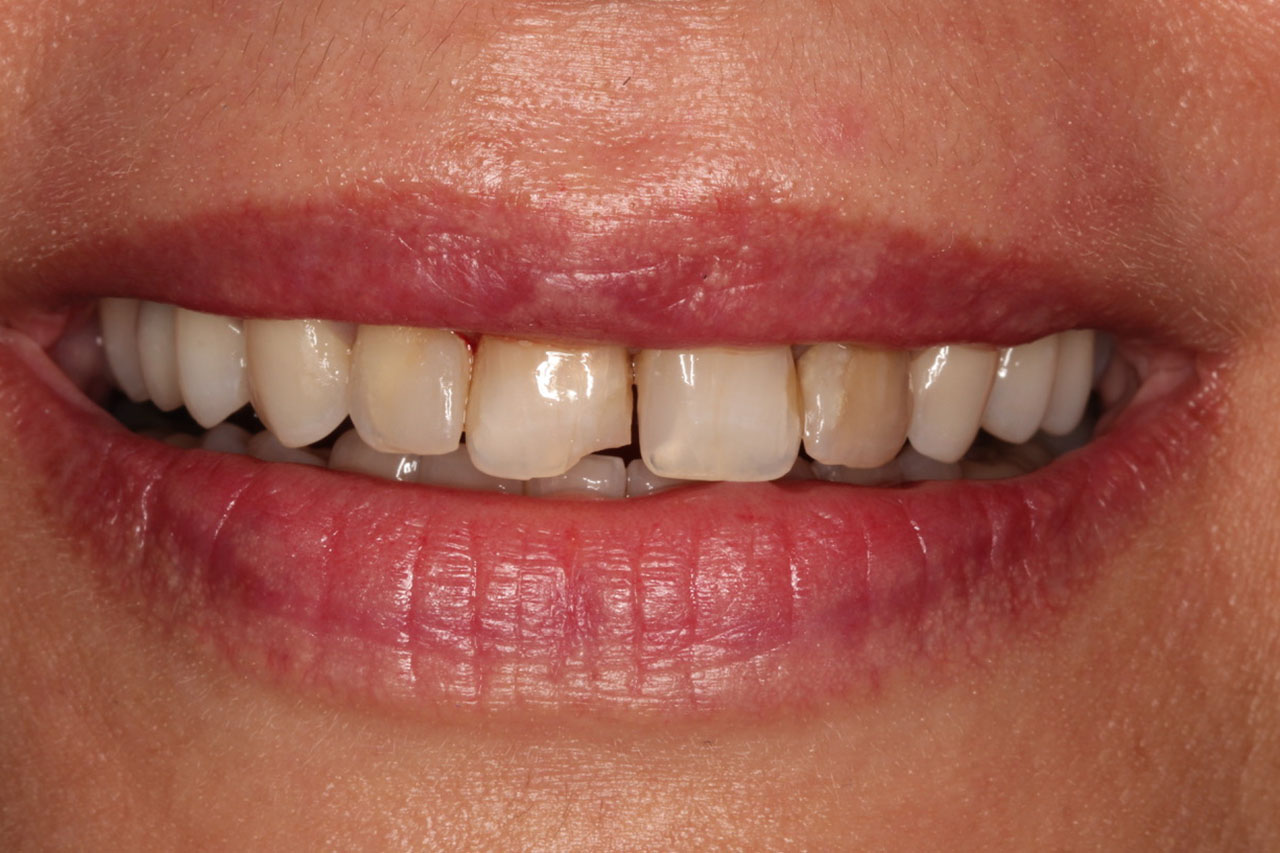

1. Korony pełnoceramiczne, nakładolicówki kompozytowe,

korony na implantach